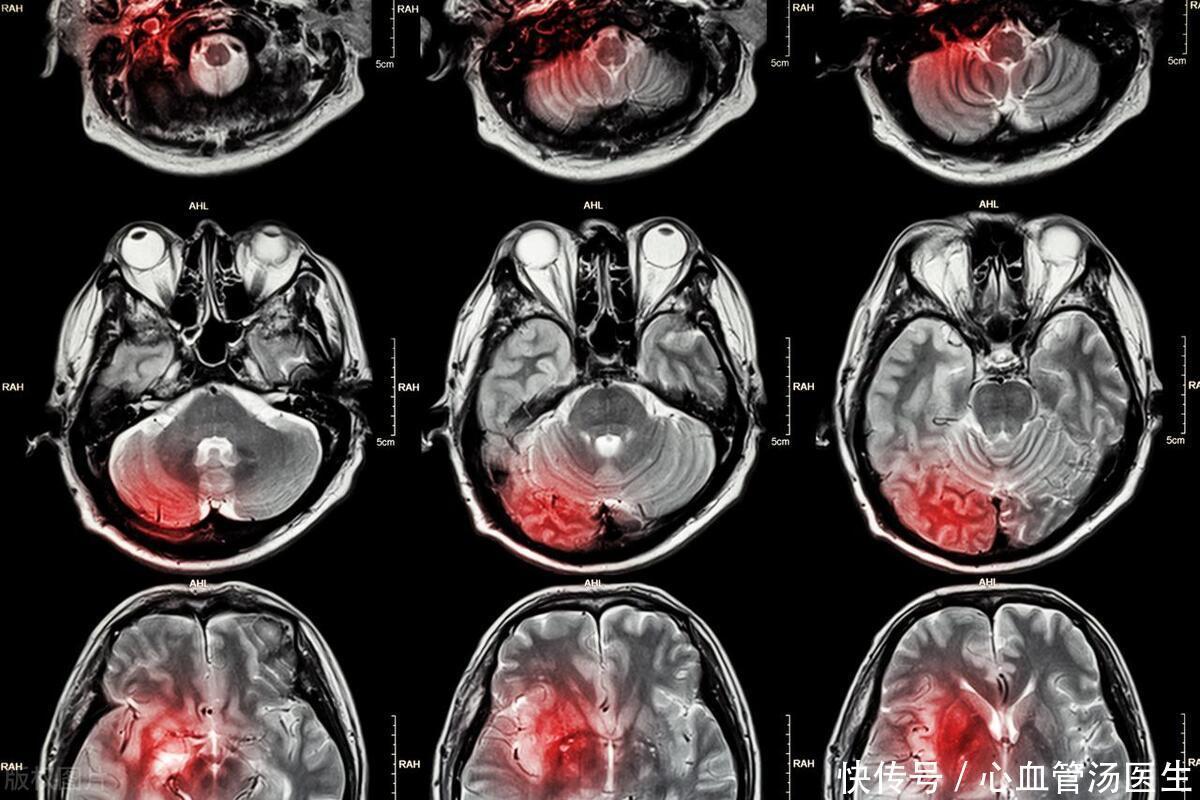

第一大类是中枢性眩晕也就是由于脑部的疾病引起常见于大脑动脉硬化、短暂脑缺血发作、小脑梗死、脑外伤、肿瘤、癫痫等对于中老年人长期高血压、糖尿病等引起的动脉粥样硬化严重容易出现上述的中枢性眩晕。

中枢性眩晕常呈持续性或者波动性和头部或身体位置的变化无关这点和耳石症等眩晕完全不同。患者发作时走路的步态不稳站立或者行走困难可能会伴有视力模糊、言语困难、吞咽困难等。